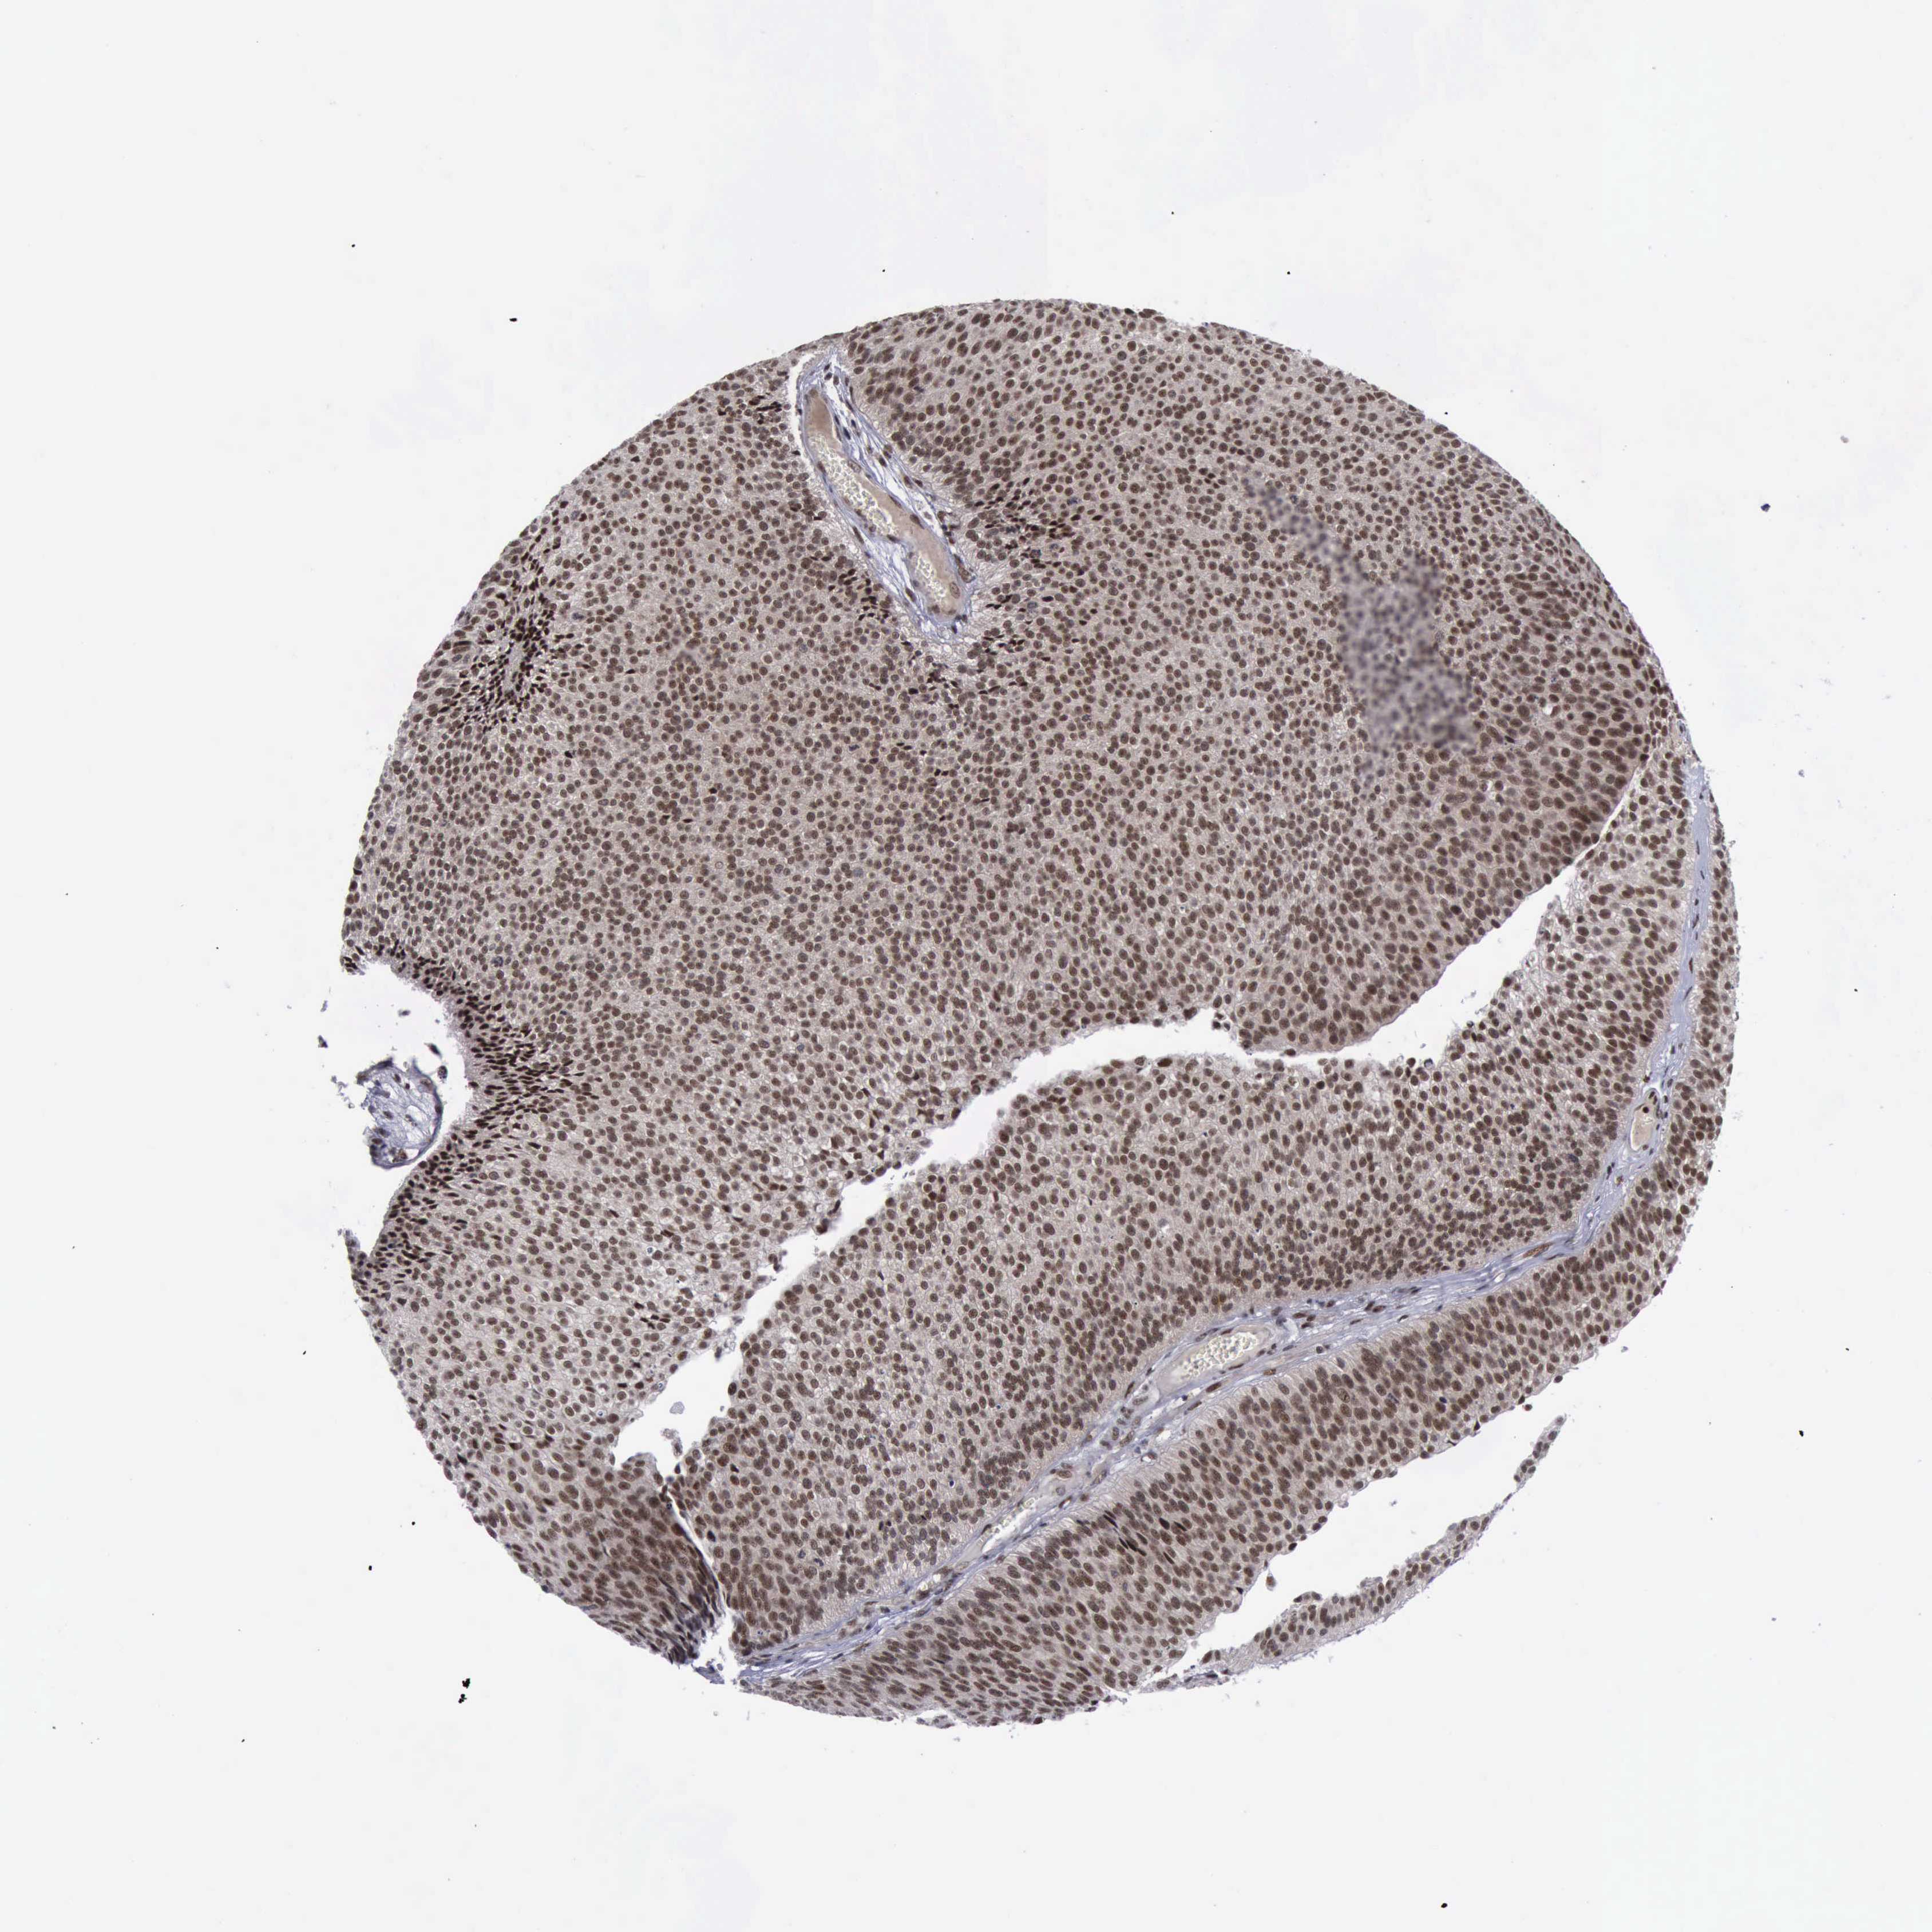

UROTHELIAL CANCER - Protein expressioni

A mouse-over function shows sample information and annotation data. Click on an image to view it in a full screen mode. Samples can be filtered based on level of antibody staining by selecting one or several of the following categories: high, medium, low and not detected. The assay and annotation is described here.

Antibody stainingi

Antibody staining in the annotated cell types in the current human tissue is reported as not detected, low, medium, or high, based on conventional immunohistochemistry profiling in selected tissues. This score is based on the combination of the staining intensity and fraction of stained cells.

Each image is clickable and will lead to virtual microscopy that enables deeper exploration of all samples and also displays staining intensity scores, fraction scores and subcellular localization as well as patient and tissue information for each sample.

Antibody CAB000102

Antibody CAB080442

Staining

High

Medium

Low

Not detected

Intensity

Strong

Moderate

Weak

Negative

Quantity

>75%

75%-25%

<25%

None

Location

Nuclear

Cytoplasmic/membranous

Cytoplasmic/membranous,nuclear

Urothelial carcinoma, High grade

Urothelial carcinoma, Low grade

Adenocarcinoma, NOS